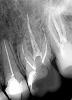

boreleno Опубликовано 10 июля, 2011 Поделиться Опубликовано 10 июля, 2011 Здравствуйте, уважаемые доктора!Оцените пожалуйста результат протезирования вкладкой.Спрашиваю т.к. возникла неприятная ситуация при лечении другого зуба в этой же клинике и получив снимки на руки хочу принять решение стоит ли продолжать протезирование у того же ортопеда. Перед тем как ставить вкладку были перепломбированы каналы, мне объяснили что все должно быть плотно запломбировано. Но в итоге на снимке треть канала выглядит пустой, что смущает Заранее огромное спасибо за комментарии! Ссылка на комментарий

Алехандро Опубликовано 12 июля, 2011 Поделиться Опубликовано 12 июля, 2011 Здравствуйте, уважаемые доктора!Оцените пожалуйста результат протезирования вкладкой.Спрашиваю т.к. возникла неприятная ситуация при лечении другого зуба в этой же клинике и получив снимки на руки хочу принять решение стоит ли продолжать протезирование у того же ортопеда. Перед тем как ставить вкладку были перепломбированы каналы, мне объяснили что все должно быть плотно запломбировано. Но в итоге на снимке треть канала выглядит пустой, что смущает Заранее огромное спасибо за комментарии! Всё отлично, не волнуйтесь, там где Вам кажется нет пломбировочного материала в канале, на самом деле не пустота, это место заполнено нерентгеноконтрастным цементом, который попросту не виден на снимке. Вкладочка сделана очень аккуратно. Ссылка на комментарий